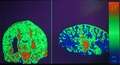

The imaging of this property is an extension of diffusion MRI. If a series of diffusion gradients (i.e. magnetic field variations in the MRI magnet) are applied that can determine at least 3 directional vectors (use of 6 different gradients is the minimum and additional gradients improve the accuracy for "off-diagonal" information), it is possible to calculate, for each voxel, a tensor (i.e. a symmetric positive definite 3×3 matrix) that describes the 3-dimensional shape of diffusion. The fiber direction is indicated by the tensor's main eigenvector. This vector can be color-coded, yielding a cartography of the tracts' position and direction (red for left-right, blue for superior-inferior, and green for anterior-posterior). The brightness is weighted by the fractional anisotropy which is a scalar measure of the degree of anisotropy in a given voxel. Mean diffusivity (MD) or trace is a scalar measure of the total diffusion within a voxel. These measures are commonly used clinically to localize white matter lesions that do not show up on other forms of clinical MRI.[58]